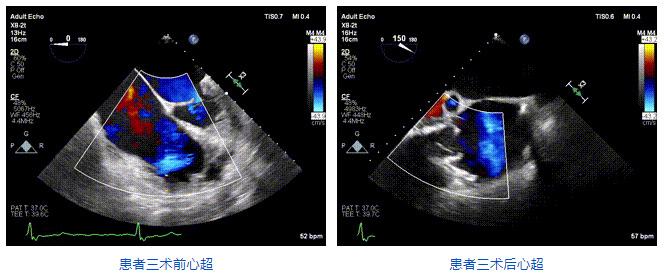

三例患者入院后,葛均波院士團隊周達新教授、潘文志教授、張源博士、陳莎莎博士及心超室的潘翠珍教授、李偉教授對患者的情況進行詳細評估和討論,最終決定為三例患者選擇LuX-Valve Plus40mm、50mm和50mm型號的瓣膜進行手術治療。手術后即刻拔除氣管插管,術后患者三尖瓣反流癥狀得到顯著改善,復查心超結果顯示人工三尖瓣瓣膜支架固定穩定,瓣葉關閉形態未見異常,未見明顯反流。